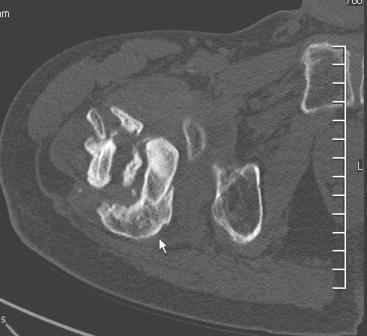

Уважаемый Глеб! Укорочение наверное побольше, да и наружно-ротационная установка скорее всего присутствует. Суставная щель прекрасная, головка живее всех живых. Ратую за подвертельную с латерализацией: исключает нарушение механической оси («исключает вальгус в коленe»), максимально удлиняет без натяжения m.iliacus. Для иллюстрации остеотомия-переделка (слава богу не автопеределка) у мужчины 65 лет.

Филипчук.

PS. Извините за качество последнего снимка, рентгенограмма выполнена по м. жительства, там где был проведен синтез. Последний снимок выполнен через 2 мес. п\о, больной без разрешения начал наступать, слава богу все обошлось.